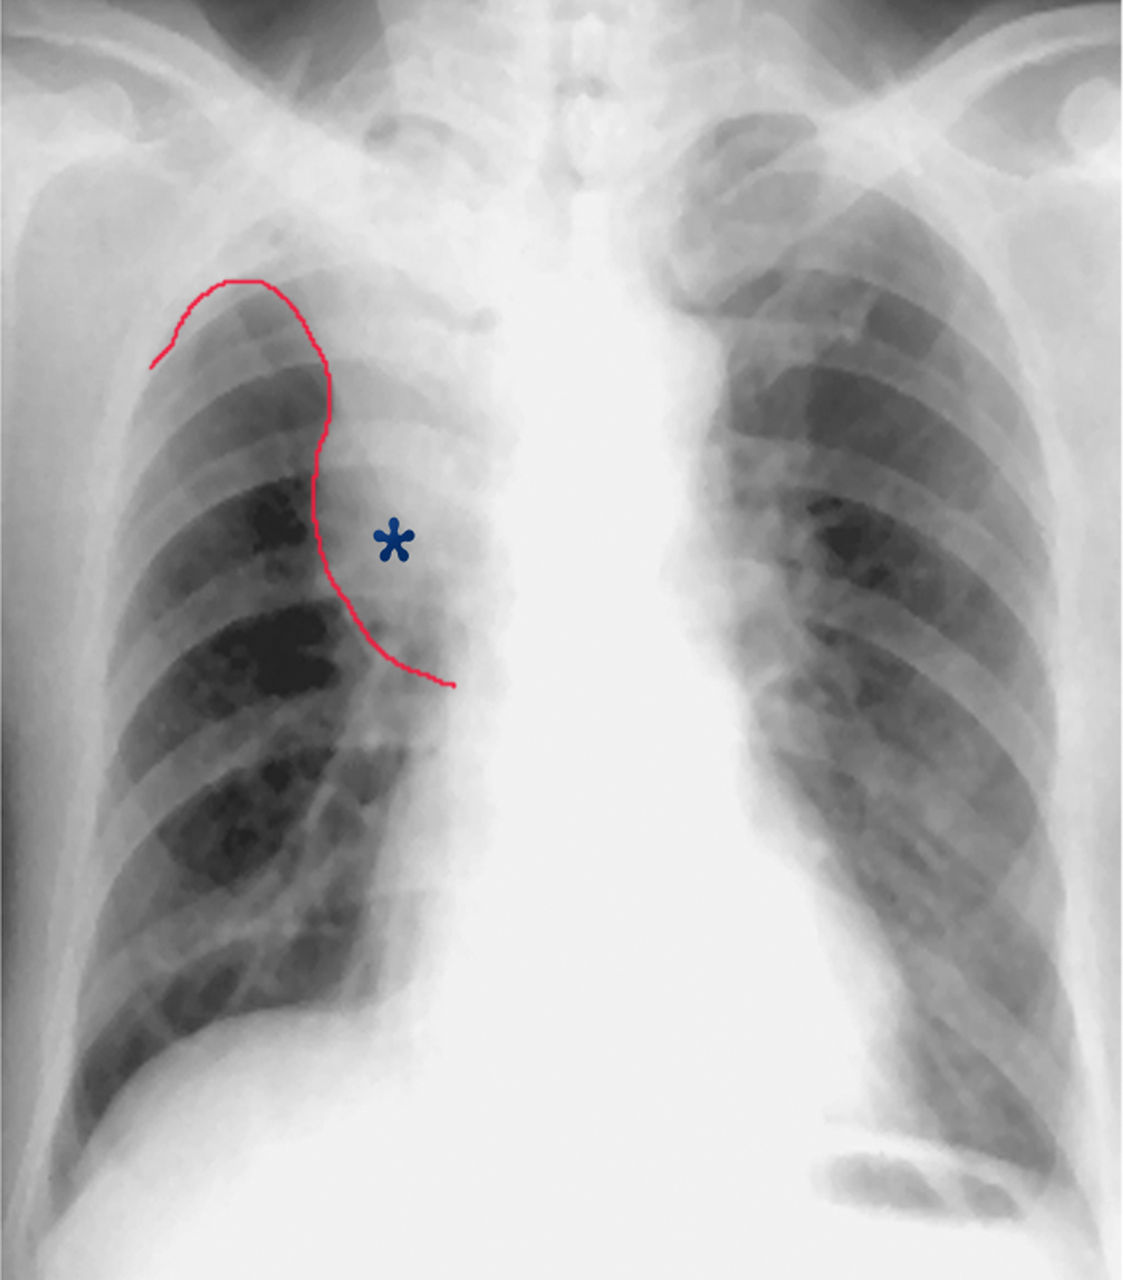

女性吸烟者的数码胸部x光片显示肺癌

典型的肺癌

(图) 大细胞中分化型肺癌